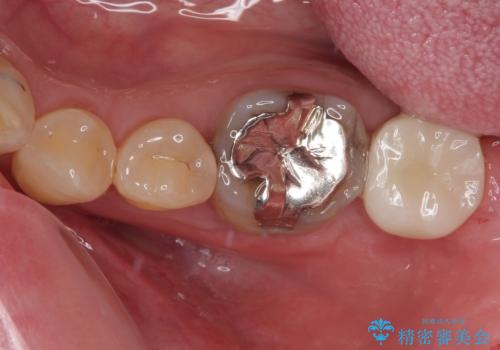

また、左下の奥歯は親知らずの影響で手前の歯の歯根までむし歯になってしまったため、親知らずとともに抜歯をし、インプラントによる補綴治療を行うこととしました。

インプラント埋入による仮歯の装着や、前歯の反対咬合の改善は比較的スムーズに達成されましたが、舌突出癖などの影響による、歯列全体のスペースを閉じることが難航し、期間がかかってしまいました。